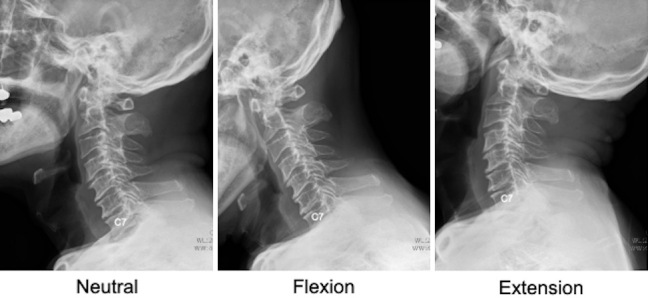

Methods: This study was a retrospective cohort analysis involving 60 patients diagnosed with cervical spine conditions and evaluated via radiographic imaging. The patients were categorized into two groups based on whether the T1 slope was clearly visible or not. Key radiographic measurements, such as the C2-C7 sagittal vertical axis (SVA) and C2-C7 Cobb angles in the neutral, flexion, and extension postures, were recorded and statistically analyzed.

Results: Significant differences were observed in the C2-C7 SVA between the groups, particularly among men. Men in the invisible T1 slope group had an average SVA of 28.9 mm, whereas those in the visible group had a mean SVA of 16.0 mm (P<0.05). Although no notable differences were observed in the Cobb angles for the neutral and flexion positions, a substantial reduction in the extension Cobb angle was noted in the invisible than in the visible group (24.4° vs. 37.6°, P<0.05).

Abstract Image